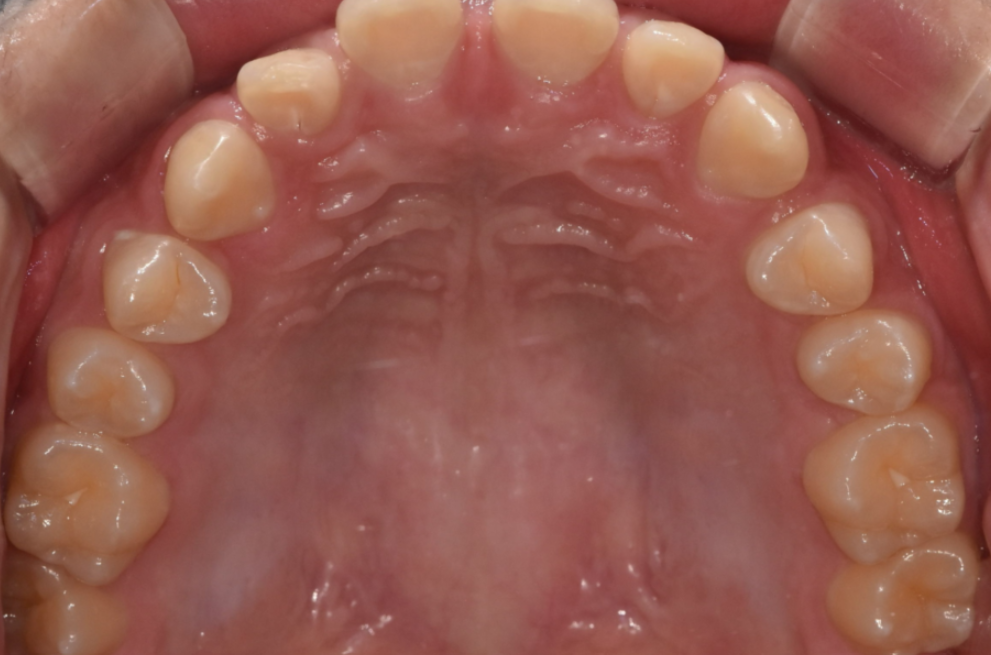

가운데 치아가 눈에 띄게 벌어져있는 환자분